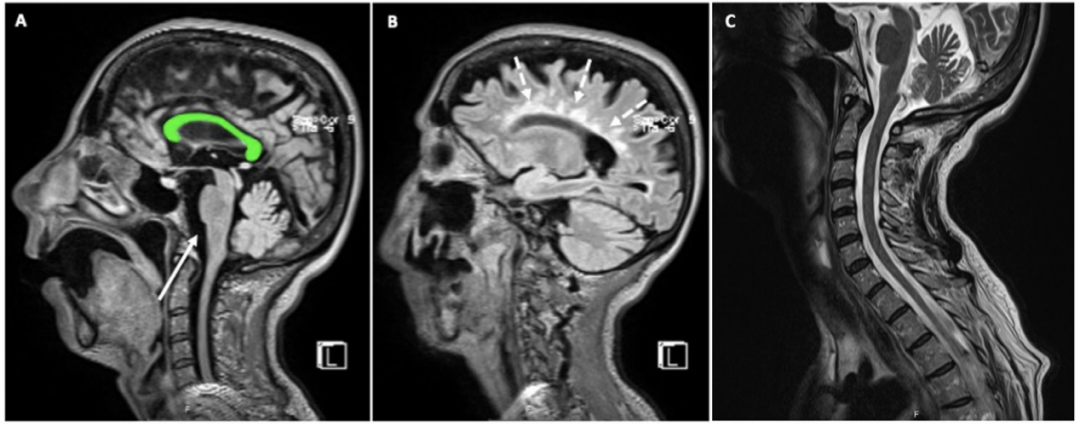

患者女性,52岁,自1999年起定期接受RRMS随访。多年来经历了多次MS复发,使用过β-干扰素、特利氟米特、芬戈利莫德等来控制病情。2018年,在用芬戈里莫德治疗(DMT疗法之一)后,患者的MS没有再复发。自发病以来的多次MRI扫描均证实了患者病情反复和累积性的白质病变(图1)。眼科OCT检查提示双侧视神经萎缩变性。同年,由于认知力下降,患者在接受神经心理学评估时发现其短时记忆障碍。同时期的神经系统检查发现其双侧视神经盘苍白,右眼持续眼球震颤,左半身4级偏瘫,左侧肢体轻度共济失调(EDSS4.0),虽然她的自主行动能力尚无大碍。

图1 患者2014年至2020年的水平位T2-FLAIR扫描显示白质病变的累积。

图2 脑和脊髓MRI。矢状位的T2-FLAIR扫描显示胼胝体萎缩(图A,绿色区域),未发现新的脑干病变(A,箭头);病变主要影响脑室周围白质(Dawson指)(图B,虚线箭头);矢状面T2加权扫描排除了颈椎束中有新的脱髓鞘病变发生(图C)。 图3 疾病发展和诊断治疗的时间线:EDSS:扩展的伤残状态量表。IFN-β:β干扰素。TFN: 特利氟米特。FNG: 芬戈利莫德。OCR: 奥克雷珠单抗。 入院时,她面容憔悴,肢体无力,只能通过平板电脑进行交流,且有蹒跚步态、咳嗽无力、反式呼吸、严重流涎、情绪不稳定的表现。体格检查发现:患者舌肌萎缩、颈部肌肉和上下肢肌肉均无力且萎缩明显,下肢还有肌痉挛表现。肌力评估:右上肢瘫痪,MRC2级,左上肢MRC3级,下肢为4级。患者深感觉、浅感觉均正常,四肢腱反射尚灵敏(3+),足底反射为屈曲。 检测患者的视觉诱发电位发现,其视神经可能存在双侧基底节前神经传导障碍,而其听觉和体感诱发电位检测未提示异常。周围神经传导无异常,针极肌电图显示运动单元明显减少,舌肌有神经再形成的迹象,慢性神经源性运动单位的电位较高。双上肢和下肢近端和远端肌肉出现急性去神经化的表现,如肌肉颤动和肌电尖波。 在对患者做了NGS测序(包括运动神经元疾病相关的的119个基因,其中82个为核基因,37个为线粒体基因),并结合DNA的半定量分析、聚合酶链反应(PCR)、实时qPCR和多重结扎依赖探针扩增(MLPA)后发现:C9orf72基因扩增阴性,但位于15q21.1上SPG11基因的两个意义不明(VUS)杂合变异通过了筛选:SPG11 (NM_025137.3) c.4669G>A(p.(Glu1557Lys))和SPG11(NM_025137.3)c.6877C>T(p.(Arg2293Trp))。前者为内含子变异,后者为错义变异,结果预测为功能丧失可能。且这两种变异在ALS 5型、痉挛性截瘫11型(SPG11)和CMT2X(Charcot-Marie-Tooth disease type 2X)的患者中都有被报道过。 综上,患者被诊断为ALS,并开始用利鲁唑治疗,后又开始用无创通气辅助呼吸,经皮内窥镜胃造口术进食等。此后,患者在家里接受物理和药物治疗,然而病情仍在不断恶化,最终于2022年5月去世。 讨论 DMT疗法显著延长了MS患者的生存期,但也为之带来了更高的罹患衰老相关的神经退行性病的风险。MS患者的肌肉萎缩,或是因为皮质脊髓束功能障碍、不活动和肌肉失用共同所致。然而,也有一些研究证实MS和ALS之间确有联系。已知C9orf72基因的重复扩增可导致脑白质脱髓鞘病变,而少数ALS患者的C9orf72基因也有六核苷酸重复扩增。一个包含了650名ALS患者入组的队列研究发现,有5名ALS患者同时患有MS(其中4位有C9orf72基因核苷酸重复扩增)。与我们的这例患者类似,文献报道的病例大都在确诊ALS之前被诊断为MS,且其中大多数是RRMS—这显然是因为MS起病年龄较小。多数患者始于肢体肌肉萎缩和肌无力,只有少数病例有横纹肌病变症状。 本病例或证明了一个不幸的巧合,或又是MS和ALS之间联系的一个例证。MS被公认为是一种神经炎性病,而ALS则被认为是一种神经退行性病。但越来越多的证据表明,ALS的神经退行性标志物如线粒体功能障碍、氧化应激和细胞骨架蛋白代谢障碍也与MS患者的病情进展有关。同时,本病例的遗传学检测结果提示SPG11的致病可能性。已有研究表明,SPG11基因敲除小鼠出现了早发性运动功能障碍和认知异常,与ALS模型动物的表型相似。从临床表现上来说,两者都会出现四肢瘫;从神经病理学上来讲,蛋白泛素化异常、p62聚集和运动神经元变性也是ALS的标志;而且SPG11基因变异也被认为是青少年ALS的遗传因素之一。SPG11基因编码spatacsin,命名源自“痉挛伴胼胝体变薄或萎缩症蛋白”,虽然生信报告提示该突变是VUS,但这一发现或会激发对SPG11表型及它与MS关系的讨论,虽然目前二者的关联并不那么直接。